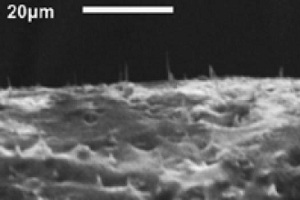

Unter dem Mikroskop: Membran mit Nano-Nadeln (Foto: ncsu.edu) |

Um die Membran mit den winzigen Spitzen zu fertigen, ziehen die Forscher zunächst Nanofasern auf einem Aluminium-Substrat. "Diese Nanofasern sind etwa zehn bis 20 Mikrometer lang", so Melechko. Dann fügen sie einen Tropfen flüssiges Silizium-Polymer hinzu, der mittels Zentrifugalkraft in eine dünne Schicht verteilt und dann gehärtet wird. Zum Schluss lösen die Wissenschaftler das Aluminium-Substrat auf, so dass das flexible Mikro-Nagelbett übrig bleibt. Die Kohlenstoff-Fasern stechen am Ende weit genug aus der Oberfläche hervor, damit sie wirklich Zellmembranen durchstechen könnten.